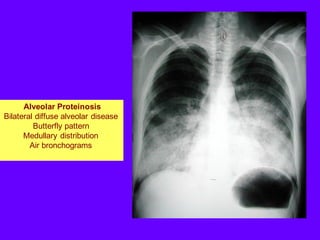

Alveolar Proteinosis

Bilateral diffuse alveolar disease

Butterfly pattern

Medullary distribution

Air bronchograms